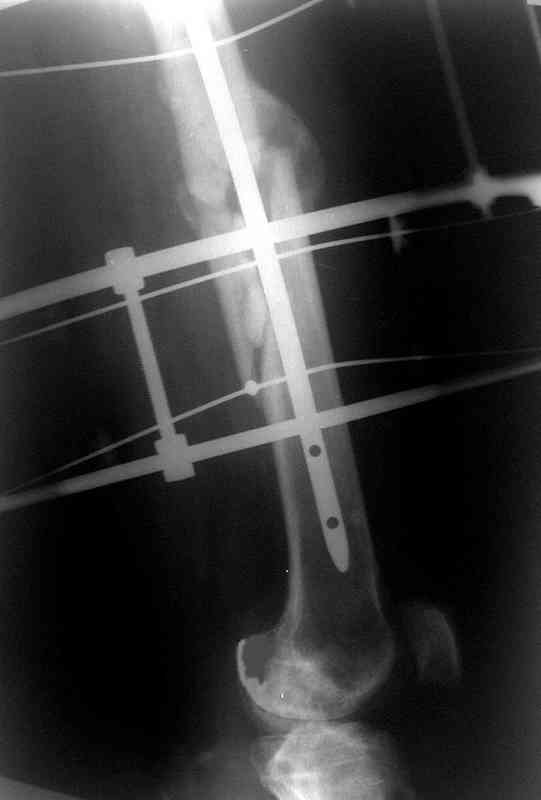

Больной А., 28 лет, поступил в НИИ им. Н.В. Склифосовского 22.12.99 после падения на улице. Жалобы на боли в области левого тазобедренного сустава и левом бедре. Из анамнеза следовало, что 20.06 во время прыжка с парашютом у него возник закрытый оскольчатый перелом средней трети левой бедренной кости со смещением отломков, по поводу чего в одной из ЦРБ Московской области через 3 дня после травмы был произведен открытый интрамедуллярный остеосинтез штифтом типа Кюнчера.

по его наружной поверхности послеоперационный рубец - рана зажила первичным натяжением. При измерении длины бедер обнаружено укорочение левого бедра на 4,5 см. На рентгенограммах этого бедра: ось конечности правильная, отмечается захождение основных костных фрагментов по длине, проксимальный конец штифта выступает слишком медиально и высоко относительно большого вертела, периостальная мозоль незначительна.22.12 - через 6 месяцев после операции, произведенной в ЦРБ, нами по поводу замедленно консолидирующего перелома левой бедренной кости с ее абсолютным укорочением под наркозом произведена операция: удаление штифта, закрытый блокирующий интрамедуллярный остеосинтез перелома левого бедра штифтом без рассверливания (UFN) длиной 40 см, диаметром 10 мм с блокированием только проксимальных отверстий (динамический остеосинтез). Наложен аппарат Илизарова на 4 полукольцах с целью удлинения укороченного бедра. Послеоперационное течение без особенностей. Ежедневно осуществляли дистракцию отломков на 1 мм. Через 3 недели после операции больной выпи-сан на амбулаторное лечение с продолжением дистракции отломков. В течение 1,5

месяцев дистракции укорочение левого бедра удалось полностью устранить. 22.02.00, т.е. через 2 месяца после повторного остеосинтеза, больному произведено дистальное блокирование штифта двумя винтами и демонтирован аппарат Илизарова. В течение 2 недель после операции больной ходил с помощью костылей, потом 2 недели с тростью. Опороспособность и функция оперированной конечности полностью восстановились через 4 недели после операции.